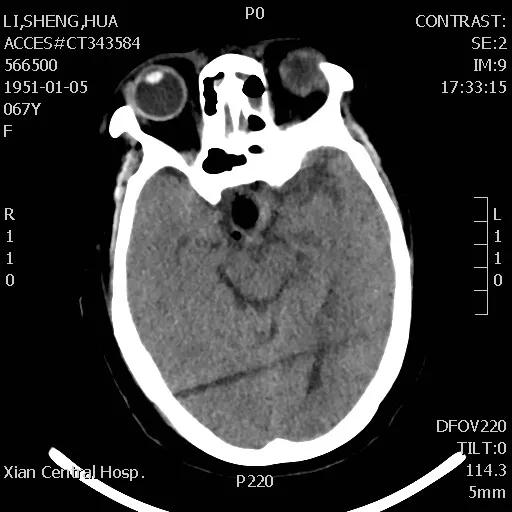

李女士头痛一年多,近日头痛加重并伴有视力迅速下降的症状,经朋友介绍,来到市中心医院神经外科王占尧主任医师处就诊。王主任通过与病人深切交谈,了解其既往病史、生活习惯、家族病史等后,均未发现有何异常,王占尧主任医师立即成立诊疗小组对李女士的情况进行分析并制定了神经内镜下手术的治疗方案。

手术于次日下午进行,整个过程非常顺利,患者预后也非常理想,术后复查CT显示肿瘤切除干净,患者视力改善明显,经过一段时间的后续治疗,患者已痊愈出院。